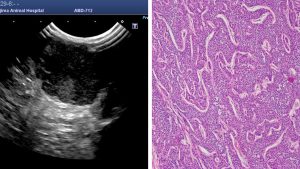

肛門嚢腺癌の超音波検査と細胞診・HE染色

皮膚超音波検査では腫瘍内には高エコーと低エコー部が混在性に観察され、時々、線状の白色構造が混じる。HE染色では高エコーの一部は腫瘍壊死に一致する。線状白色構造は結合組織に増生に概ね一致する。細胞診では小型の上皮性細胞が集簇し、神経内分泌を思わせるような裸核細胞が混じている。HE染色ではロゼット様の配列が見られる。